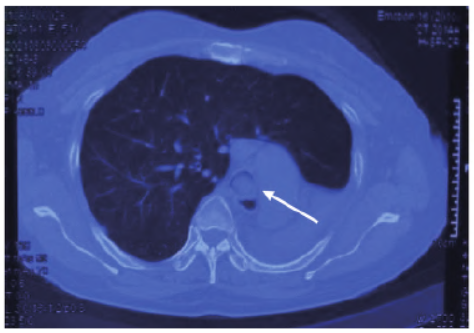

图1患者外院胸部CT检查(2021年8月3日)。注:正气道占位(箭头所指),纵隔左偏,左肺不张